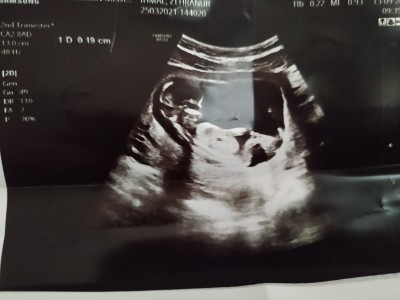

Hamilelikte cinsiyet tahmini :))

tahmin alabilir miyim

bebek-gebelik-hamilelik-cinsiyet-tahmin-

Kaç haftalık canım

13+3 haftalık